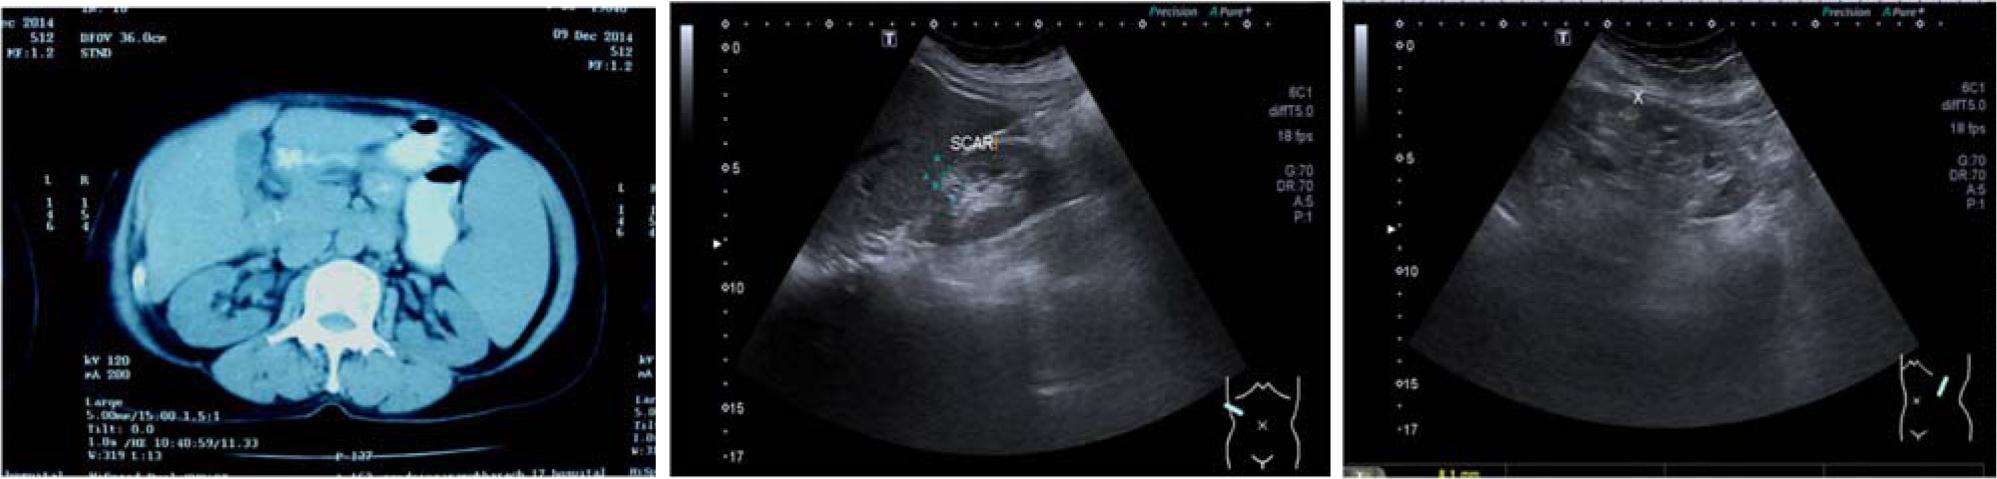

Figure 1

Figure 2